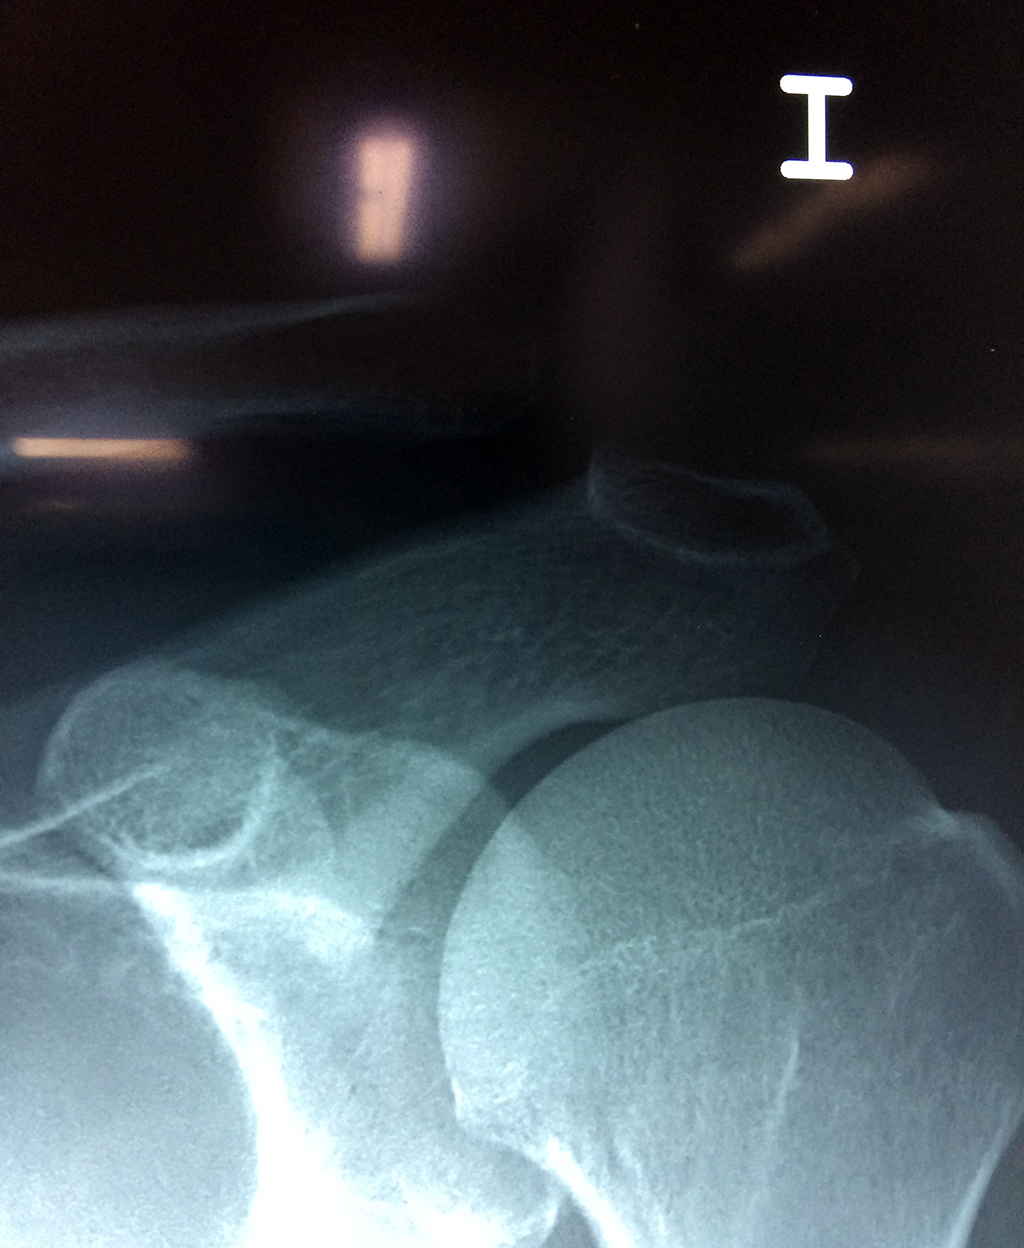

Clavicula 1

Detail Download